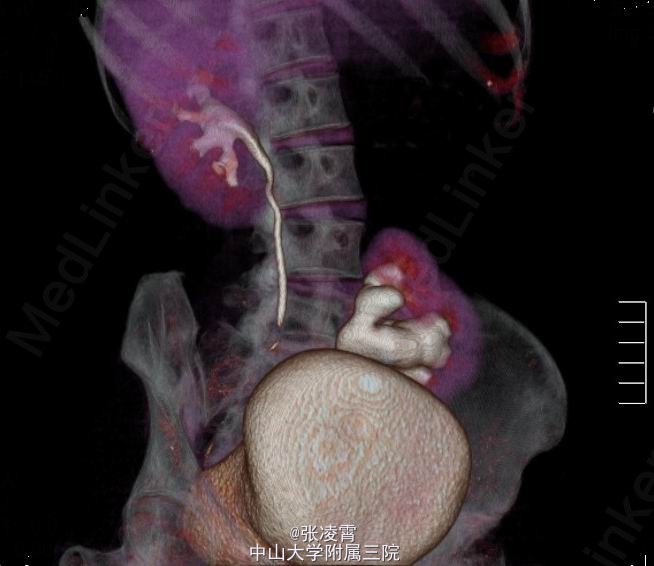

体格检查:体温37.2oC,心率82次/min,呼吸19次/min,血压110/80,皮肤黏膜、巩膜无黄染,全身浅表淋巴结无肿大,心肺未见异常,双肾区无红肿、隆起,左下腹可扪及一边缘清楚的实性包块,呈椭圆形,大小约13x8cm,压痛(+),反跳痛(-)。左肾区叩击痛(-),左肾肋脊点,肋腰点压痛(-),右侧肋脊点、肋腰点压痛(-)。腹平软,左侧输尿管走行区压痛(-),右侧输尿管走行区压痛(-),膀胱区无膨隆,压痛阴性,双侧腹股沟区未触及肿物。 实验室检查:血、大便常规,血生化,胸片,心电图均无明显异常。尿常规:血细胞(++),白细胞(++)尿沉渣白细胞计数252个/μl。 影像学检查:双肾、盆腔螺旋CT平扫+增强扫描+计算机四维成像提示:左肾位于腰4~骶2椎体水平,左肾盂交界处可见一大小约21x18mm高密度结节,边界锐利,左肾盂、肾盏扩张,4条左肾动脉分别起自腹主动脉、右侧髂总动脉及左侧髂内动脉,左肾静脉汇入右肾静脉。左输尿管较对侧短,无明显扩张,双肾形态、大小正常,肾实质未见异常密度影,增强扫描未见强化。右肾盂、肾盏、输尿管无明显扩张,膀胱充盈良好,壁光滑,腔内未见异常充盈缺损。